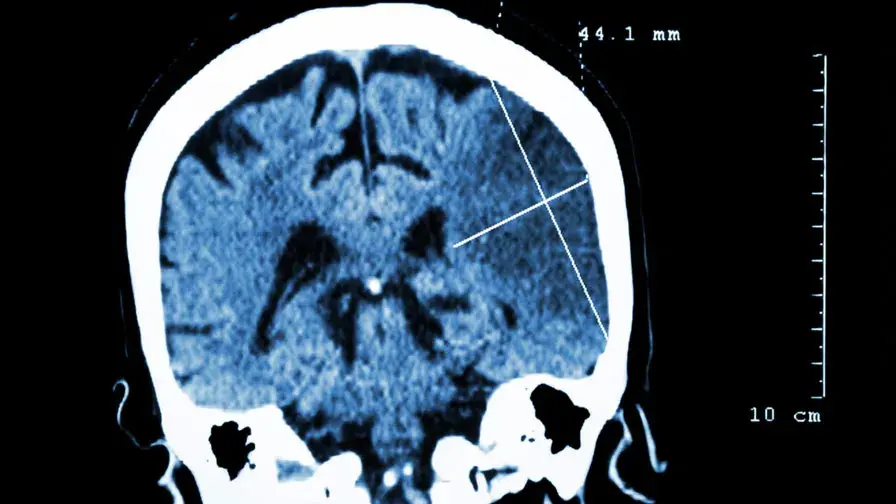

La prise en charge urgente des accidents ischémiques transitoires permettrait une réduction de 50% du risque d’AVC.

• Une étude internationale coordonnée par le Pr Amarenco – hôpital Bichat, AP-HP – et menée dans 21 pays différents a montré une réduction de 50% du risque d’accident vasculaire cérébral – AVC – après un accident ischémique transitoire - AIT, grâce à une prise en charge dans les 24 heures suivant les premiers symptômes. Les résultats sont encore meilleurs si la prise en charge se fait dans une structure spécialisée.